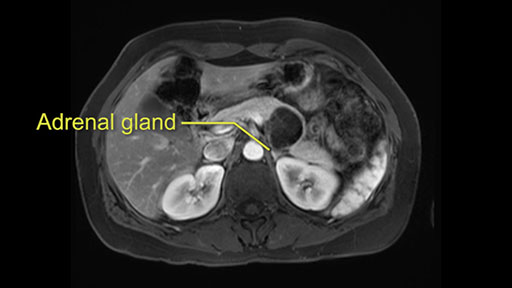

The lesion also is quite posterior. While the plane between the cyst and the left adrenal gland is often preserved, we do have to pay attention here so that we remain in the right plane and maintain our margin here. Occasionally in these cases, en bloc adrenalectomy needs to be performed.

Sometimes with even benign lesions of the spleen you can have quite a lot of inflammation in the retroperitoneum and so I do think about and wonder whether I will have some difficulty in the retroperitoneum and I usually look at the scan for that purpose. It looks like there is no inflammation in the retroperitoneum. It does look very close to the patient’s left adrenal gland but knowing the planes and suspecting that there isn’t any active inflammation, this should be able to come off the left adrenal gland without any difficulty. But obviously prepared to take some of the left adrenal if that’s necessary in this procedure. So those are my procedure-specific slowing down moments in a distal pancreatectomy when I’m considering a laparoscopic approach. I think the patient-specific slowing down moments in this particular case I have discussed with the procedure-specific moments. I don’t really see any other issue or that I have to be careful of or consider.

So first, I'll show you the scan. Here's the traditional view, where you see the cyst, which is in the body of the pancreas. And you see over here, it's got a quite thick wall. And going a little bit back also, here you see a septation which is very important, because I think a septation is what separates this from, for instance, the pseudocyst of the pancreatitis. And also the location of the cyst you see here, abutting the adrenal gland and going down a bit more, it's also quite close to a bowel loop. So when thinking about this cyst: female, the location in the body of the pancreas, thick wall, septation, and as you can read in history, it was basically asymptomatic, so no signs of pancreatitis. So, this probably all points towards a mucinous cystic neoplasm.

So what I would normally do in these patients, I would look at the abutment of any other organs, one, which is here, potentially the adrenal gland and two the small bowel. And two, look at the distance from the vessels which I would normally do in a coronal view. So you can easily measure the distance and third I look at the insertion of the inferior mesenteric vein. Now we can probably also see that on here. Although it's better on a CT scan and it's better on a coronal view, you want to know where the inferior mesenteric vein comes into either the splenic or the SMV, because that is typically a very important slow down moment when you mobilize the lower portion of the pancreas knowing where the inferior mesenteric vein comes in either the splenic vein or the SMV. So those are I think the three most important points for the CT scan.

After you've slung the pancreas, to the left of the cyst, and if you encounter any adrenal involvement later after you have transected the pancreas and you move to the left side of the patient towards the spleen, take either the entire or partial left adrenal gland with the resection. If you go underneath the adrenal gland, and it's probably best to do a full RAMPS (Radical Antegrade Modular Pancreatosplenectomy) procedure, that is where you take the Gerota’s fascia completely onto the mucinous cyst. And that's very crucial to get a radical resection if you think the adrenal gland is involved.